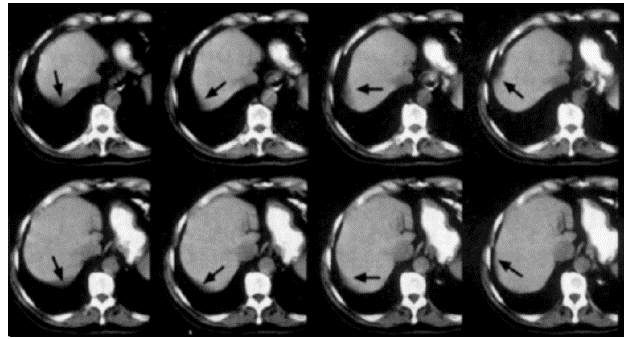

This image shows the effect of the kVp on image contrast. Note the differences between 100 and 120 kVP. The higher the kVp, the lower the contrast, known as low contrast resolution.

Low contrast detection is used to examine structures with low contrast such as the brain or the abdomen. This is accomplished by using higher kVp.

CR and Slice Thickness

These images demonstrate that the thicker the slice, the lower the contrast resolution. Although in general, an image with a thicker slice contains more x-ray photons (or less noise), the partial volume effect can reduce the visibility of smaller objects.

Motion Artifacts

Motion artifacts are caused by the patient or tissue movement such as breathing or peristalsis. These types of artifacts have been greatly improved because of the speed in multi-slice scanning used today.

Faster scanners have improved motion as the patient has less time to move during the scan. This can be accomplished with faster gantry rotation or more x-ray sources. Compare these two images for motion. The image on the right has a much better resolution than the one on the left.

Motion artifacts can be reduced by using special reconstruction techniques. 10% is added to the 360-degree standard rotation. Repeated projections are averaged which reduces motion artifacts. The image on the left shows less motion when this technique is used.